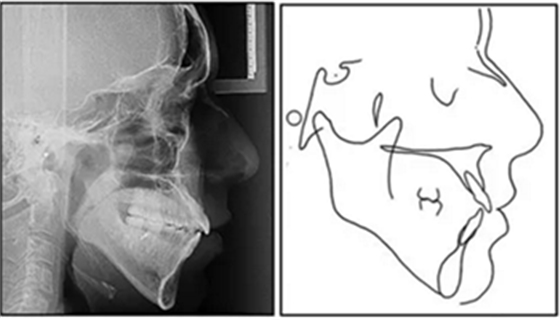

影像學:全景片示:牙根平行度可。頭顱側位片及疊加圖示:下頜骨發(fā)生逆時針旋轉,面部輪廓改善;上切牙轉矩正常,下切牙輕微舌傾;唇突度減小,鼻唇角增大。